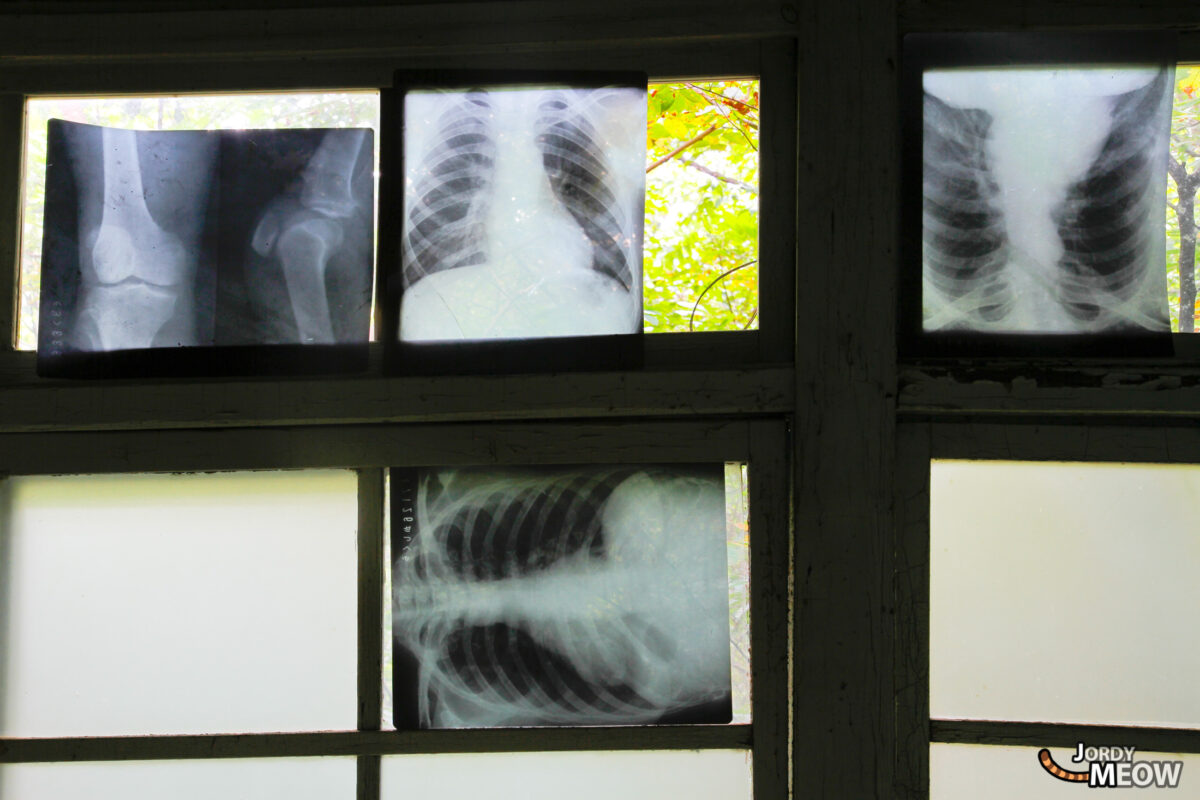

The Nichitsu Clinic is the first abandoned hospital I went to. Since I went to many more, you can see more of them here: Abandoned Hospitals in Japan and Little Abandoned Japanese Clinics.

This infamous doctor’s office also contains human organs, and among them, the horrendous Nichitsu Brain! But it seems somebody stole it, unfortunately.

The hospital also changed a lot between 2010 and 2017, but it is still fun to explore.

And the operating room, which used to have a surgical light.